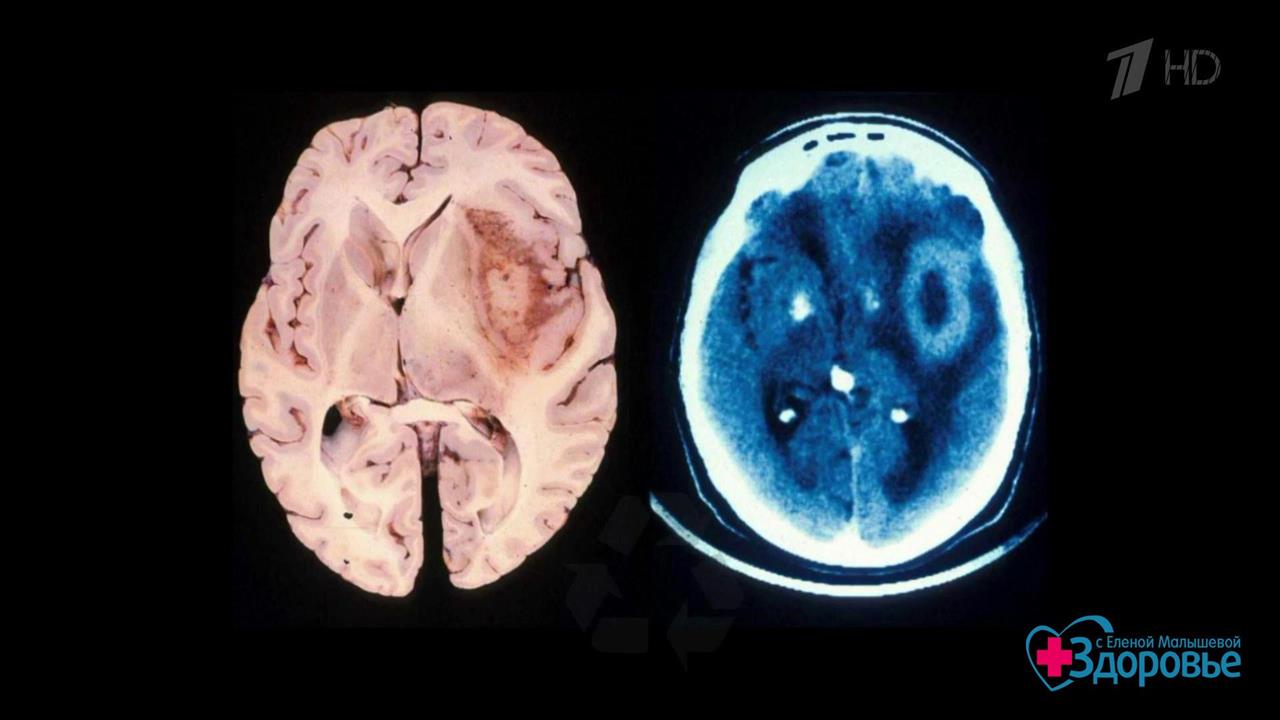

Недавно на совещании с президентом РФ директор Института молекулярной биологии им. В.А. Энгельгардта Александр Макаров рассказал об экспериментальной технологии уничтожения злокачественных опухолей с помощью вирусов. Открытие российских ученых дарит надежду сотням людей с раком, в том числе актрисе и телеведущей Анастасии Заворотнюк, у которой диагностировали глиобластому. Что это за технология? В студии – доктор биологических наук, профессор Института молекулярной биологии Петр Чумаков.